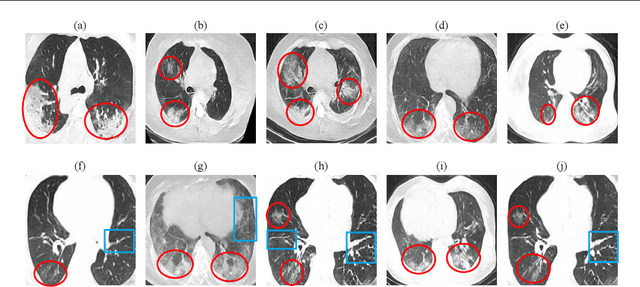

Radiographic images offer an alternative method for the rapid screening and monitoring of Coronavirus Disease 2019 (COVID-19) patients. This approach is limited by the shortage of radiology experts who can provide a timely interpretation of these images. Motivated by this challenge, our paper proposes a novel learning architecture, called Detail-Oriented Capsule Networks (DECAPS), for the automatic diagnosis of COVID-19 from Computed Tomography (CT) scans. Our network combines the strength of Capsule Networks with several architecture improvements meant to boost classification accuracies. First, DECAPS uses an Inverted Dynamic Routing mechanism which increases model stability by preventing the passage of information from non-descriptive regions. Second, DECAPS employs a Peekaboo training procedure which uses a two-stage patch crop and drop strategy to encourage the network to generate activation maps for every target concept. The network then uses the activation maps to focus on regions of interest and combines both coarse and fine-grained representations of the data. Finally, we use a data augmentation method based on conditional generative adversarial networks to deal with the issue of data scarcity. Our model achieves 84.3% precision, 91.5% recall, and 96.1% area under the ROC curve, significantly outperforming state-of-the-art methods. We compare the performance of the DECAPS model with three experienced, well-trained thoracic radiologists and show that the architecture significantly outperforms them. While further studies on larger datasets are required to confirm this finding, our results imply that architectures like DECAPS can be used to assist radiologists in the CT scan mediated diagnosis of COVID-19.